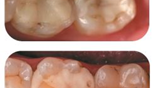

ЗАЧЕМ менять старую пломбу, если она еще не выпала?